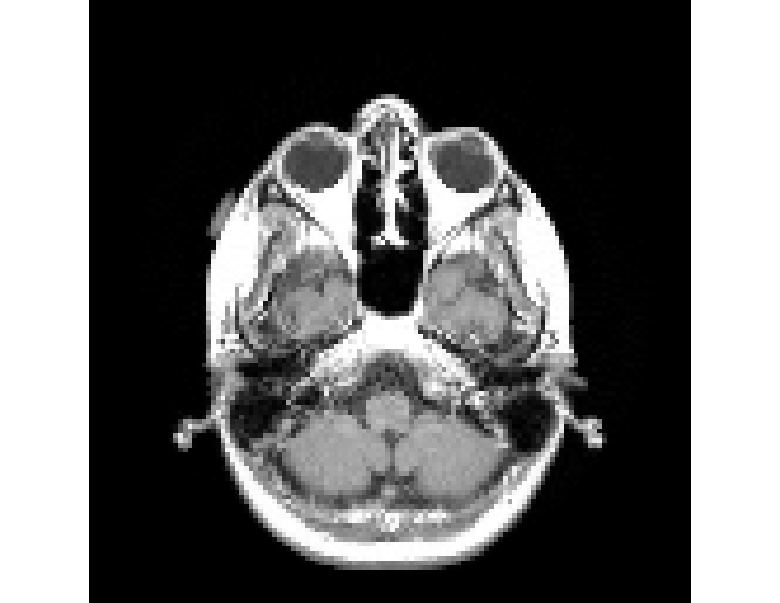

Refer to caption

(h) DDM

(i) Original density profile

(j) kk-NN

Figure I.3: Representative original and reconstructed density profiles for the Hughes 2D pedestrian model dataset (M=200×50M=200\times 50). Left column panels show the original density profile, while panels 3(b), 3(d), 3(f), 3(h) and 3(j) show its reconstructions, obtained with the five decoders: RANDSMAP-RFF with P=NP=N, RANDSMAP-MS-RFF with P=NP=N, RANDSMAP-Sig with P=NP=N, DDM and kk-NN, respectively. For the RANDSMAP decoders, the displayed configuration is the one achieving the lowest training error among all variants of that type (see full comparison in Fig. 4(a)).